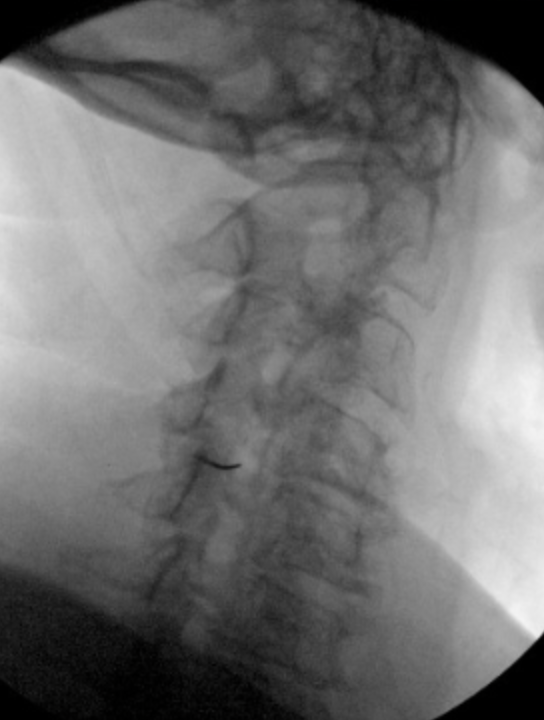

I went Caudal tilt until I saw disc space (**For a cervical Transforaminal)

55 Oblique, till I saw SAP. Hit SAP, walked off, took AP (lateral to unicnate process)

Made sure pre-op MRI that vert was not in way.

Looks good. Poking EJ not the worst thing, though 5 deg more/less of oblique still probably gives you a good trajectory and off the EJ. Def no more medial.

Nice job. I try to avoid all vasculature. If you look at your MRI, superficial vessels will be in the way. Try not to penetrate internal carotid, need to look at more than the vertebral artery alone IMO. Reviewing MRI and measuring planned trajectories, there have been a number of times IC in the way, especially upper cervical. Need to be able to identify. For those cases I use a modified lateral approach. Use small gauge needles. What size needle is that by the way? Looks 22 in oblique but 25 in AP.

25 2.5